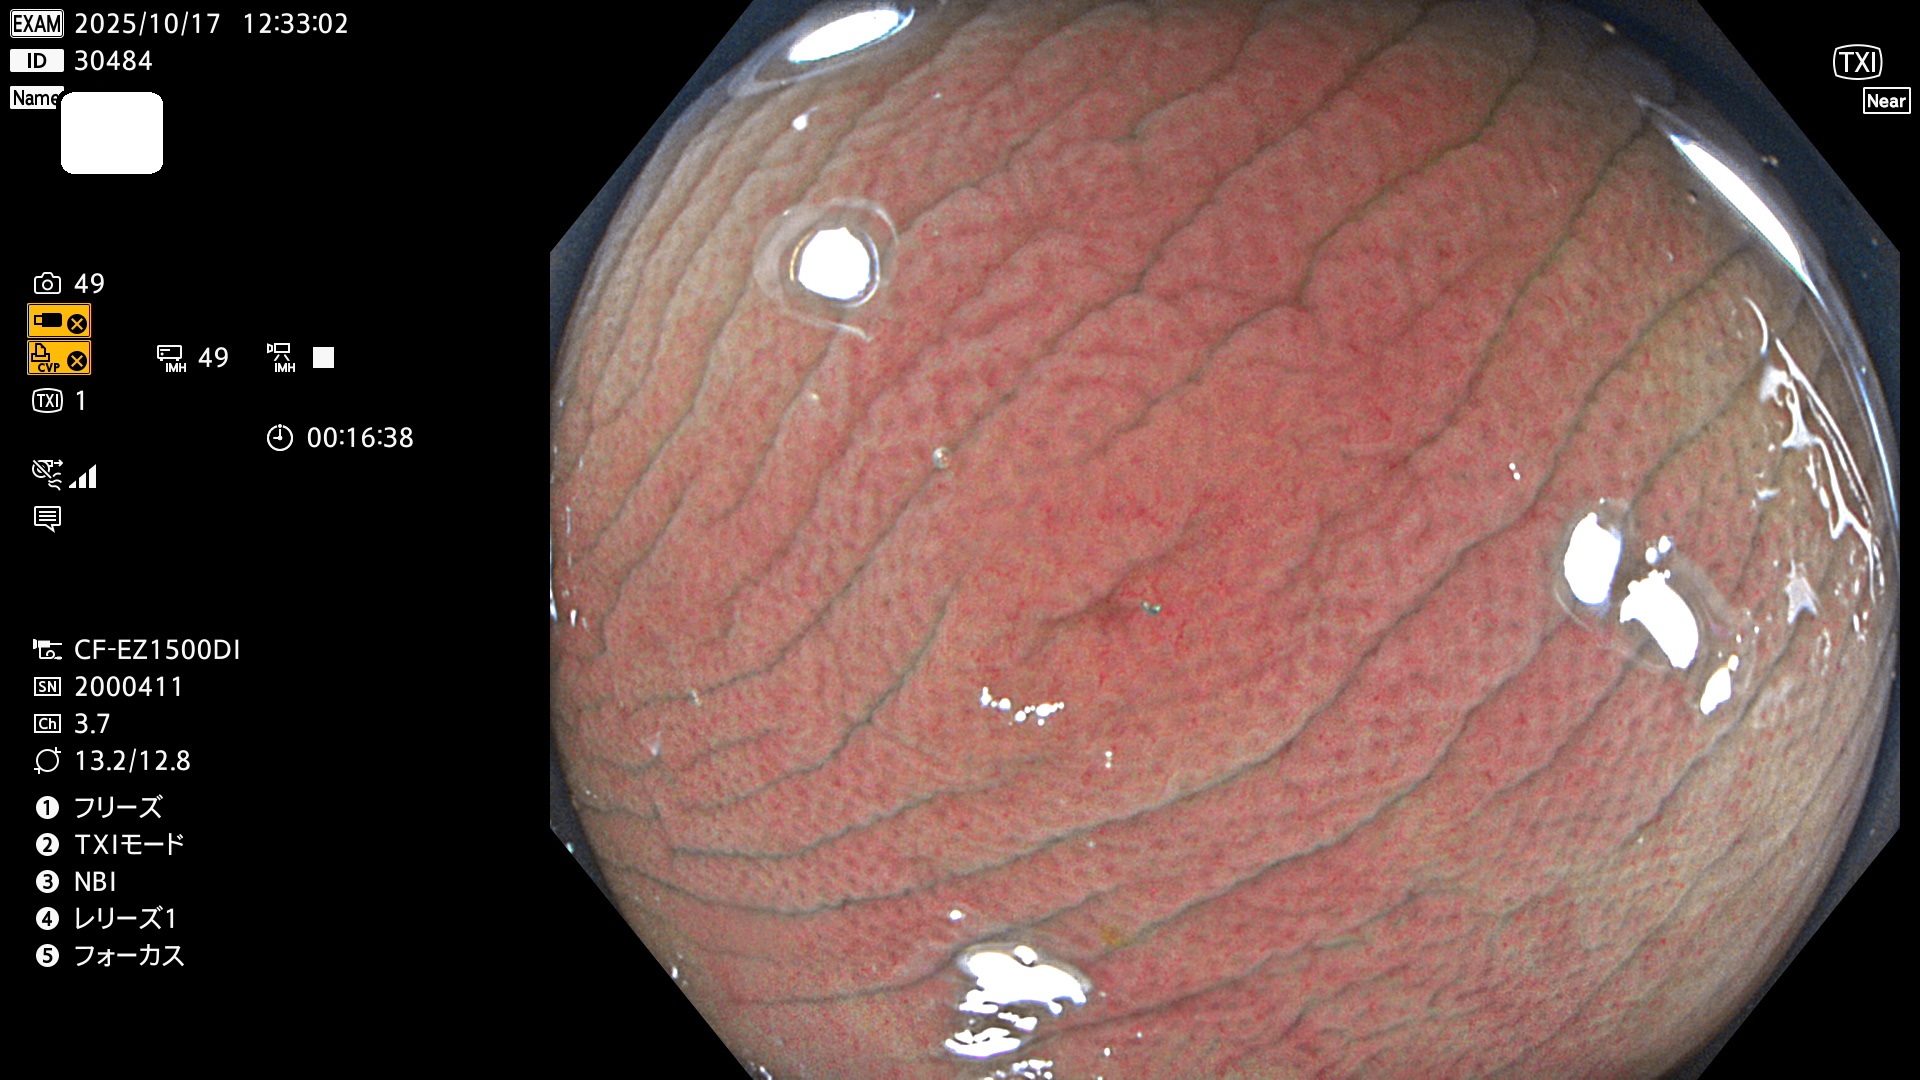

完全に平坦な物をUb、陥凹している物をUcと呼びます。Ubは認識が困難で、Ucはびらん(炎症)と紛らわしいために見落とされやすく、「内視鏡後・大腸癌」の原因になります。

専門的)Uc=De Novo癌? 内視鏡の解像度が低かった時代、このような説もありました。しかし今日の高精度内視鏡では良性の微小なUc型腺腫(APC遺伝子異常の腺腫)が日常的に見つかります。Ucこそが多段階発癌(Adenoma-Carcinoma Sequence)のMain Routeです。

2025年10月16日〜10月19日の4日間(40件)2個 (Uc_ADR=2個/40人=5%)